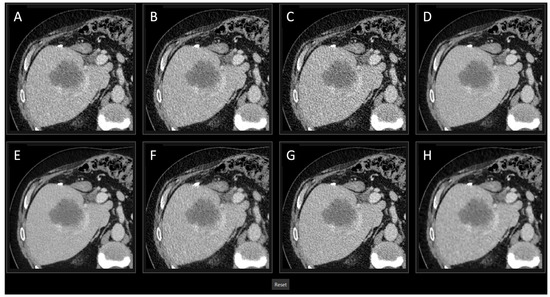

2.5.1. First Part

| This study | 28 | 0–17 | 33 | chest, abdomen and pelvis staging | art. and pv. | - GE Revolution with stagging protocol (voltage: 120 kVp, slice thickness 0.625 mm) - Reconstructions: FBP, ASIR-V (30%, 50%, 70%, 100%), Pixelshine (Soft, Ultrasoft), DLIR (High, Medium, Low) - Evaluation: qualitative analysis of ranked image quality on a scale from 1 (best) to 8 (worst); qualitative analysis of image interpretation, structural differentiability, and diagnostic certainty for ASIR-V 50%, ASIR-V 100% DLIR-High and DLIR-Low using a 5-point Likert scale; quantitative analysis of SNR and CNR | - Qualitative: DLIR-High ranked highest, followed by DLIR-Medium and DLIR-Low; ASIR-V 50%, Pixelshine Soft, and Ultrasoft were mid-ranked, with FBP and ASIR-V 100% at the bottom; DLIR-High is preferred for all three criteria (image interpretation, diagnostic certainty, and structural differentiability), followed by DLIR-Low, ASIR-V 50%, and ASIR-V 100%. - No significant difference in evaluation between younger and older radiologists, or between arterial and portal venous phases. - Quantitative: SNR and CNR (best to worst)—DLIR-High = ASIR-V 100%, DLIR-Medium = ASIR-V 70%, DLIR-Low = PS Ultrasoft = ASIR-V 50%, PS Soft, ASIR-V 30%, FBP; DLIR-High and ASIR-V 100% showed the highest SNR- and CNR-values with the lowest noise. |